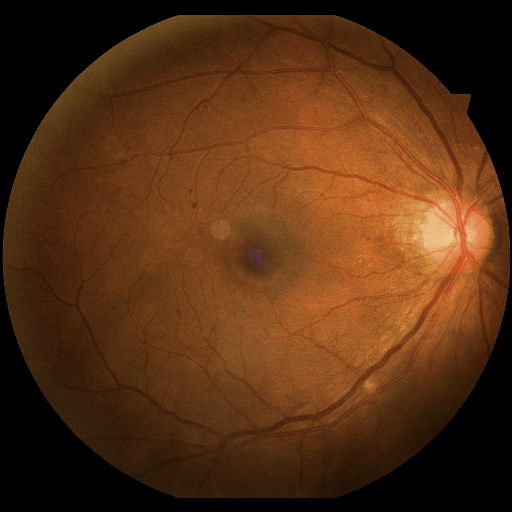

We conducted a case study on diagnosing diabetic retinopathy with ensembles of DL models. For benchmarking the performance of our ensemble-based solutions under the scheme described in Sec.3.3, we used two popular collections of diabetic retinopathy image data, the Kaggle Diabetic Retinopathy dataset [22] (hereafter referred to as “Kaggle-DR”) and the Messidor-2 dataset [23], each respectively consisting of and high resolution images. Diabetic retinopathy is graded into five SLs, as displayed in Figure 2. Following the problem setup used in previous papers [24], we trained models to distinguish the referable (SL2-4) cases from the non-referable ones (SL0 & SL1) (see Section B.1 for more detailed descriptions). We also tested our trained ensemble models on two o.o.d. image datasets (ImageNet [25] and CIFAR-10 [26]) to examine their capabilities of identifying o.o.d. inputs (see Section B in the supplementary materials).

The Kaggle-DR dataset comprises high resolution images. The presence of diabetic retinopathy is rated into five different SLs: no-DR (SL0), mild (SL1), moderate (SL2), severe (SL3), and proliferate (SL4), as illustrated in Figure 2. We divided the Kaggle-DR dataset into a development set and a test set, which respectively consisted of and images. The data in the development set were used to train and validate our Deep Learning (DL) models. The Messidor-2 dataset [38] that consisted of images was also used in our experiment as an additional dataset to test the true generalization performance of the models trained on the Kaggle-DR dataset. Images in Messidor-2 dataset were graded into the five SLs as in the Kaggle-DR dataset. Figure S.1 provides an illustration of the datasets used in our experiments.